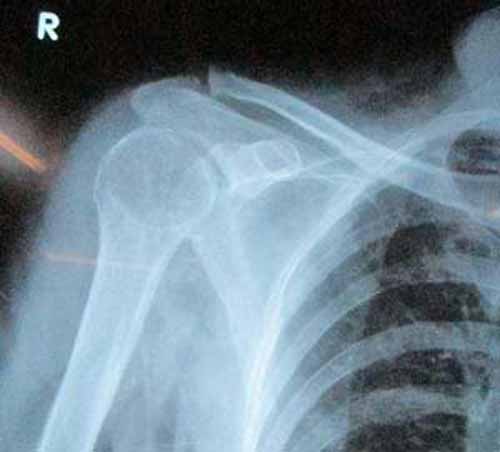

三个疗程后,马奶奶受损关节的肿胀全部消失,疼痛感消退,双肘可以灵活弯曲,肩臂能自由抬举,双手可以写字、端碗,X线片显示肩关节的骨密度恢复正常,受损关节部位的骨质恢复正常,膝盖的变形趋势也得到控制,可以正常行走。

(图:X线显示马奶奶右肩关节骨质恢复正常)